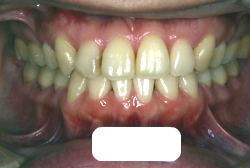

「上の前歯の凸凹」という主訴で来院したケースです。確かに上の左右二番目の歯が内側に引っ込んでいて、凸凹が目立つ状態です。歯並びの凸凹を矯正学では 叢生(そうせい)と言いまして、確かにご本人的にはそこが気になるのですが、矯正学的には前歯の前突の方がより問題となるケースです。

初診時の写真をご覧いただくと、何となく前歯が前傾しているのが感じられると思うのですが、よく見ると上の歯だけでなく、下の前歯も前傾しているのがわかります。このように上の前歯も下の前歯も両方外向きになっている症状のことを、「上下顎前突」と言います。こういうケースの場合は上下左右の小臼歯を抜く(つまり4本抜歯する)ことで配列の中に隙間を作り、その隙間を利用して配列を揃えるだけでなく、 前歯を内側に入れていく治療をします。

治療前後の口元の変化です。前歯の角度が大きく変わりました。治療前は外向きの前歯に押されて、口元がふくらみすぎの状態でした。黄色の線は鼻の頂上と顎の先端を結んだ線で、審美線と言います。審美線と唇はあまり接触しない方が良いと考えられています。矢印の部分がかなりラインオーバーしています。治療後はよりスマートで美しい横顔になりました。このように歯並びを直すと、唇の表情ひいてはお顔全体の表情にも良い変化が生まれます。